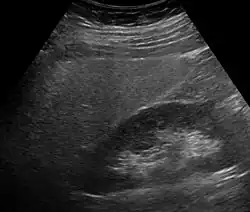

Imaging studies are often obtained during the evaluation process. Ultrasonography reveals a "bright" liver with increased echogenicity. Pocket-sized ultrasound devices might be used as point-of-care screening tools to diagnose liver steatosis.[30] Medical imaging can aid in diagnosis of fatty liver; fatty livers have lower density than spleens on computed tomography (CT), and fat appears bright in T1-weighted magnetic resonance images (MRIs). Magnetic resonance elastography, a variant of magnetic resonance imaging, is investigated as a non-invasive method to diagnose fibrosis progression.[31]

Histological diagnosis by liver biopsy is the most accurate measure of fibrosis and liver fat progression as of 2018.[8] Conventional imaging methods, such as ultrasound, CT and MRI, are not specific enough to detect fatty liver disease unless fat occupies at least 30% of the liver volume.[32]